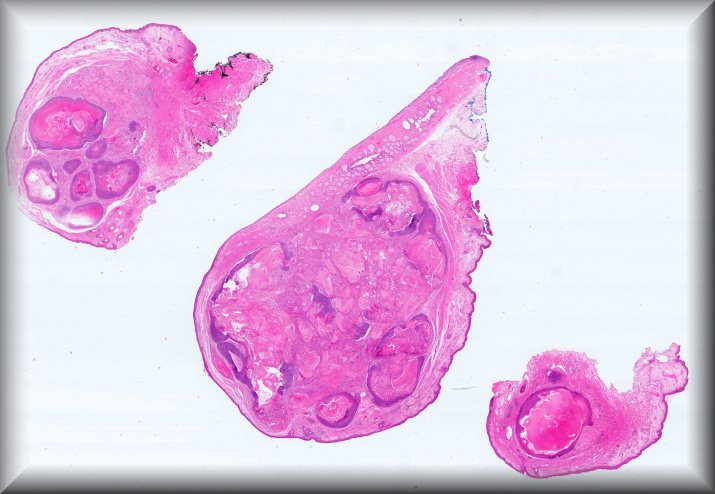

Fiona Roberts (Glasgow): 9 year old female with buphthalmos secondary to congential glaucoma. Protocol |